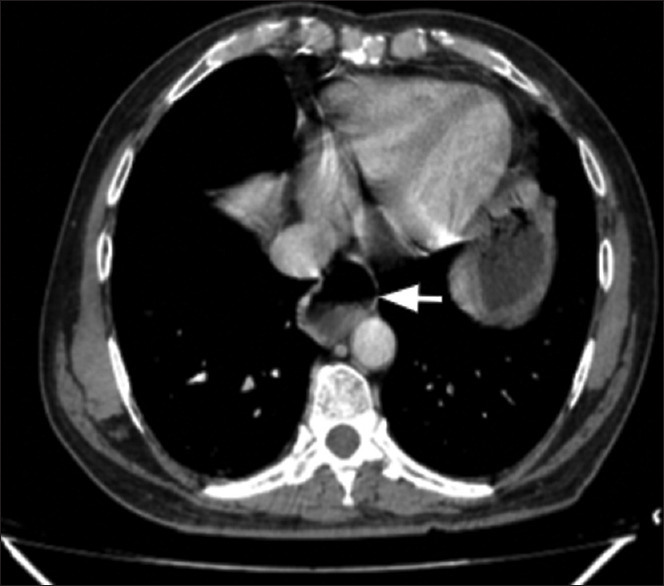

导读:在过去的十年中,随着腹腔镜抗反流手术(LARS)的数量和可接受性在长期医学治疗中不断增加,因此,盆底包裹术的并发症间歇性地出现胃灼热和吞咽困难的复发症状。内窥镜检查和钡餐是初步调查进行怀疑眼底包裹失败。然而,随着多层计算机断层扫描(CT)和多平面重建的容易获得以及对钡检查的熟悉程度的降低,外科医生熟悉包膜失败的各种表现将是谨慎的。目前,还没有公认的标准来报告应用程序封装失败。我们对使用CT扫描治疗基底膜包裹失败的文献进行了全面的回顾,并与著名的放射科医生和外科医生组成了一个多学科的疝气小组,讨论了CT扫描在治疗可疑包裹失败中的作用。在完成了对大约43例包膜失败患者的初步研究后,我们创建了一个标准的CT报告格式,这有助于我们管理即使是最复杂的病例。这个标准的报告格式可以被全世界的受训者和外科医生使用。这将导致报告的一致性,将有助于决策,也将有助于创建国家和国际主要包装失败和重做基金申请注册。患者与方法:对43例多层螺旋CT膜片失效患者进行评价,分析膜片失效类型及膜片完整性维持的影响因素。采用一种新颖的结构化报告清单来描述术后影像学发现。结果:描述了患者的人口学特征、术后影像学和术中表现。不同类型的包装失败-阻碍类型和相关病理分析相对频率在包装失败。新颖的结构化报告包括LARS术后患者的包裹完整性和失败并发症。结论:眼底包裹失败是LARS术后常见的并发症。一种新的结构报告与检查表将帮助外科医生评估术后复发症状的患者。多层螺旋CT是初步内镜评估后疑似包裹失败的理想成像方式。冠状面和矢状面重建的多平面成像有助于了解包裹层的完整性及其检测故障/迁移的能力。

Introduction: With increasing numbers and acceptability of laparoscopic anti-reflux surgery (LARS) procedures over long-term medical treatment in the past decade, it follows that the complications of fundoplication wrap are seen intermittently with recurrent symptoms of heartburn and dysphagia. Endoscopy and barium swallow are the initial investigations performed for suspected fundoplication wrap failures. However, with easy availability of multislice computed tomography (CT) and the multiplanar reconstructions along with reduction in familiarity with barium examinations, it would be prudent for the surgeons to familiarise themselves with various appearances of wrap failure. Currently, there is no accepted standard to report a fundoplication wrap failure. We did a thorough literature review on the use of CT scans for fundoplication wrap failure, created a multidisciplinary hernia team with prominent radiologists and surgeons and discussed the role of CT scans in the management of suspected wrap failure. After completing a pilot study with around 43 patients of wrap failure, we created a standard CT reporting format which helped us in the management of even the most complex cases. This standard reporting format can be used by trainees and surgeons worldwide. This would lead to uniformity in reporting, would help in decision-making and would also help create national and international primary wrap failure and redo fundoplication registry.

Patients and methods: A total of 43 patients of wrap failure of multislice CT evaluation were analysed for type of failure along with factors responsible for the maintenance of integrity of the wrap. A novel checklist with structured reporting was used for the description of the post-operative imaging findings.

Results: The demographic characteristics, post-operative imaging and intraoperative findings were described. The different types of wrap failure - Hinder types and associated pathologies were analysed for relative frequency in wrap failures. The novel structured reporting included wrap integrity and failure complications in post-operative patients of LARS.

Conclusion: Fundoplication wrap failure is not an uncommon complication seen after LARS. A novel structured report with checklist will help the surgeons to evaluate the post-operative patient with recurrent symptoms. Multislice CT is the ideal modality for imaging suspected wrap failures after primary endoscopic evaluation. Multiplanar imaging with coronal and sagittal reconstructions is useful for understanding the integrity of the wrap and its ability to detect failure/migration.